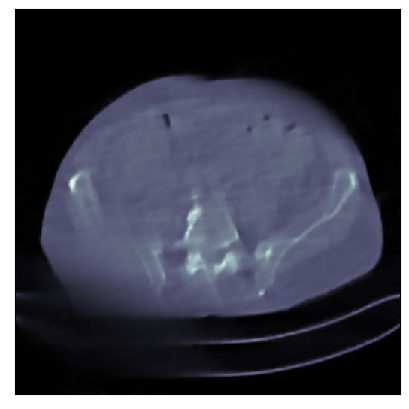

We consider the variational reconstruction framework for inverse problems and propose to learn a data-adaptive input-convex neural network (ICNN) as the regularization functional. The ICNN-based convex regularizer is trained adversarially to discern ground-truth images from unregularized reconstructions. Convexity of the regularizer is desirable since (i) one can establish analytical convergence guarantees for the corresponding variational reconstruction problem and (ii) devise efficient and provable algorithms for reconstruction. In particular, we show that the optimal solution to the variational problem converges to the ground-truth if the penalty parameter decays sub-linearly with respect to the norm of the noise. Further, we prove the existence of a sub-gradient-based algorithm that leads to a monotonically decreasing error in the parameter space with iterations. To demonstrate the performance of our approach for solving inverse problems, we consider the tasks of deblurring natural images and reconstructing images in computed tomography (CT), and show that the proposed convex regularizer is at least competitive with and sometimes superior to state-of-the-art data-driven techniques for inverse problems.